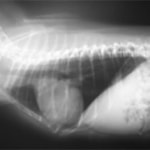

症例:【マルチーズ 12歳齢 去勢オス】

D:胸部レントゲン写真 正面像

E:胸部レントゲン写真 側面像

左側胸壁心尖部領域を最強点とするLevine 5/6の収縮期性心雑音が聴取された。

胸部レントゲン検査において重度の心拡大と肺水腫が認められた。超音波検査では、重度の僧帽弁閉鎖不全症、三尖弁閉鎖不全症、中程度の大動脈弁閉鎖不全症を合併していることが判明した。三尖弁逆流速度から肺高血圧症が示唆された。

ACE阻害薬、ピモベンダン、硝酸イソソルビド徐放剤、ベラプロストナトリウム、利尿剤としてフロセミドとスピロノラクトンを用いて治療を行った。